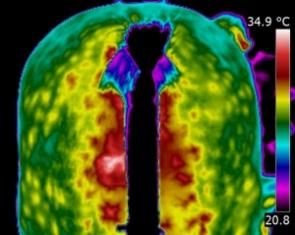

Anatomic

imaging such as Ultrasound, X-ray or MRI test and reveal the actual

state of structure and anatomy; a broken bone or tear in a structure

such as a tendon. These diagnostics are necessary to reveal the nature

and degree of breakdown that has already occurred in tissue. Physiologic

imaging is a function of metabolic action and reveals the physiology of

tissue as it is occurring now. Physiologic images can change and might

appear prior to anatomic disruption. Thermography (or thermal imaging)

is considered physiological imaging. Anatomic imaging is needed for

diagnosis after thermal (physiologic) imaging has pinpointed a problem

area.